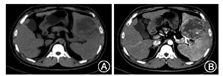

患者女,59岁,因间断性左上腹部疼痛1周入院。既往体健。查体:脾脏异常增大,左上腹部压痛,余未见异常。实验室检查:白细胞4.46×109/L,红细胞4.03×1012/L,血红蛋白107 g/L,血小板102×109/L;肿瘤标志物正常。腹彩提示:脾内实质性略强回声光团,回声欠均。腹部CT提示:脾脏明显增大,内见类圆形肿块影,大小约12.2 cm×9.4 cm,病灶密度不均,其内见斑片状更低密度影,动脉期不均匀强化,静脉期、延迟期逐渐充填,其内低密度始终未见强化(图1A、图1B)。术前诊断:脾占位性病变。患者全麻下行脾切除术。术中探查见脾肿大,质地柔软,颜色正常,周围未见异常粘连,脾门未见淋巴结肿大。病理报告:脾脏标本14 cm×13 cm×8.6 cm,切面见灶状、放射状、灰白色、实性、质韧区,余切面红褐色、实性、质软;镜下见肿瘤细胞呈上皮样生长,其间可见小的分支血管形成,细胞内血管腔形成水泡细胞(图2A, 图2B, 图2C);免疫组化结果:CD31(+),CD34(+),Ki-67(约+10%)(图2D, 图2E, 图2F)。病理诊断:脾上皮样血管内皮细胞瘤,伴出血和坏死。